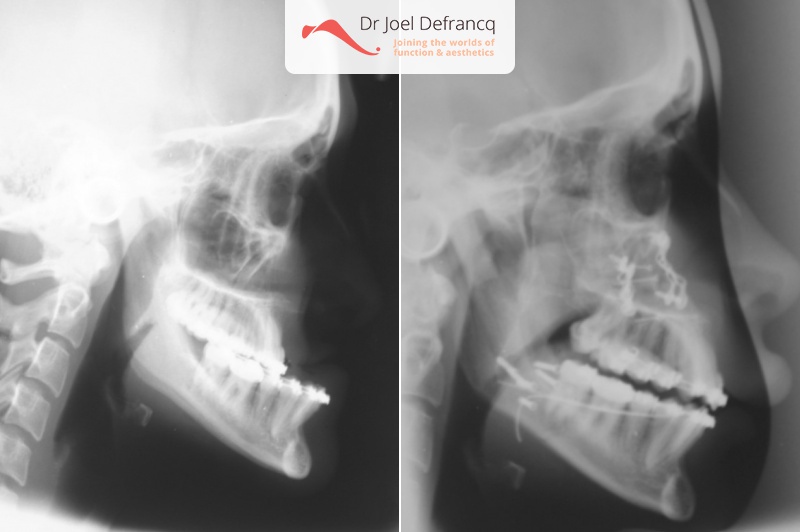

Crilke: too long lower jaw

- Te grote onderkaak (Onderbeet)

- Te kleine bovenkaak

- Te korte bovenkaak

- Klasse III

- Verkorting onderkaak (BSSO)

- Verlenging bovenkaak (Le Fort I)